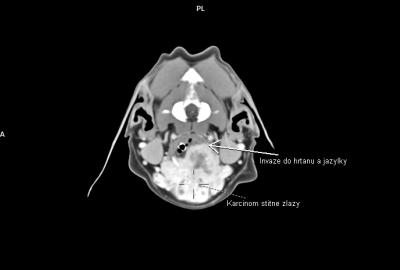

V regionu hrtanu jednoznačně vedou nádory štítné žlázy(thyreoidey). Často se jedná o zhoubné varianty (karcinomy) s lokální invazivitou do struktur hrtanu a jazylky, s tendencí k tvorbě metastáz-mediastinum, plíce. Patří ale zároveň k nádorům poměrně často operovatelným. CT pak hraje v takovýchto případech zásadní diagnostickou roli.